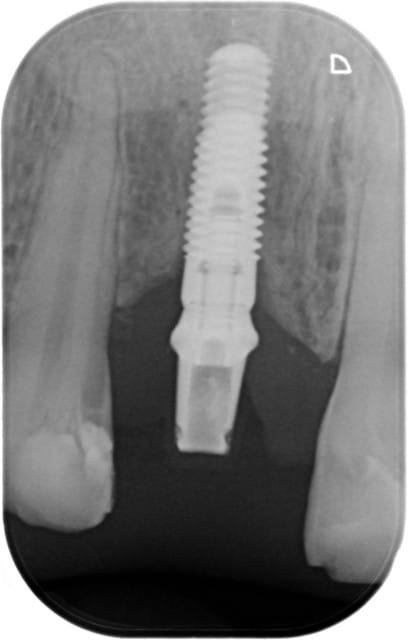

Un patient est venu voir mon associée avec cet implant en bouche depuis 3 ans au niveau de la 11. Motif de la consultation: perte de la couronne provisoire (oui, je sais, 3 ans...)

Sauriez-vous me dire de quel implant il s'agit ? De plus, j'ai un doute au niveau de son pronostic. Ah oui, il a arrêté de fumer il y a 1 an...

pour l'implant c'est un TSV Zimmer....;-)

sûr à 100%...malgré le fait que l'on ne fait que deviner le trou ovale dans la zone apicale...

quel pronostic?...amha pas particulièrement de problème même s'il y a une petite perte osseuse au col...

si la gencive est belle il a de nombreuses années devant lui...